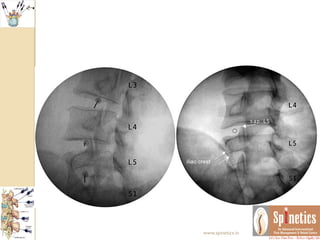

Unusual case

 A male 42 years had acute excruciating leg and back pain

 He was a hard worker laborer

 Financial issues

 Govt hospital resistance

 Subjected to pain management after lots of consents

 Within 24 hours, Injected transforaminal ozone after

confirmation with non ionic contrast

 Waited for few minutes till any untowards events to

occur

 With comfortable vital parameters, planning to shift him

in recovery area, rather he immidiately walk out pain free

 Even long term followup kept to see any reoccurance

 Neurological behaviour differs in same presenting

spine conditions

 Even though we repeated MRI in one month span as

there is no reccurance what it suggest

 There is resolving annular tear with sequestration

 Many of our patients we routinely found such

herniations which might be too painful to the

patients

 In opposite this patient was not having any

symptoms regarding reccurance of pain

 This the follow-up of more than 2and half years

Unusual case  Amale 42 years had acute excruciating leg and back pain  He was a hard worker laborer  Financial issues  Govt hospital resistance  Subjected to pain management after lots of consents  Within 24 hours, Injected transforaminal ozone after confirmation with non ionic contrast  Waited for few minutes till any untowards events to occur  With comfortable vital parameters, planning to shift him in recovery area, rather he immidiately walk out pain free  Even long term followup kept to see any reoccurance www.spinetics.in

Unusual case  Neurologicalbehaviour differs in same presenting spine conditions  Even though we repeated MRI in one month span as there is no reccurance what it suggest  There is resolving annular tear with sequestration  Many of our patients we routinely found such herniations which might be too painful to the patients  In opposite this patient was not having any symptoms regarding reccurance of pain  This the follow-up of more than 2and half years www.spinetics.in